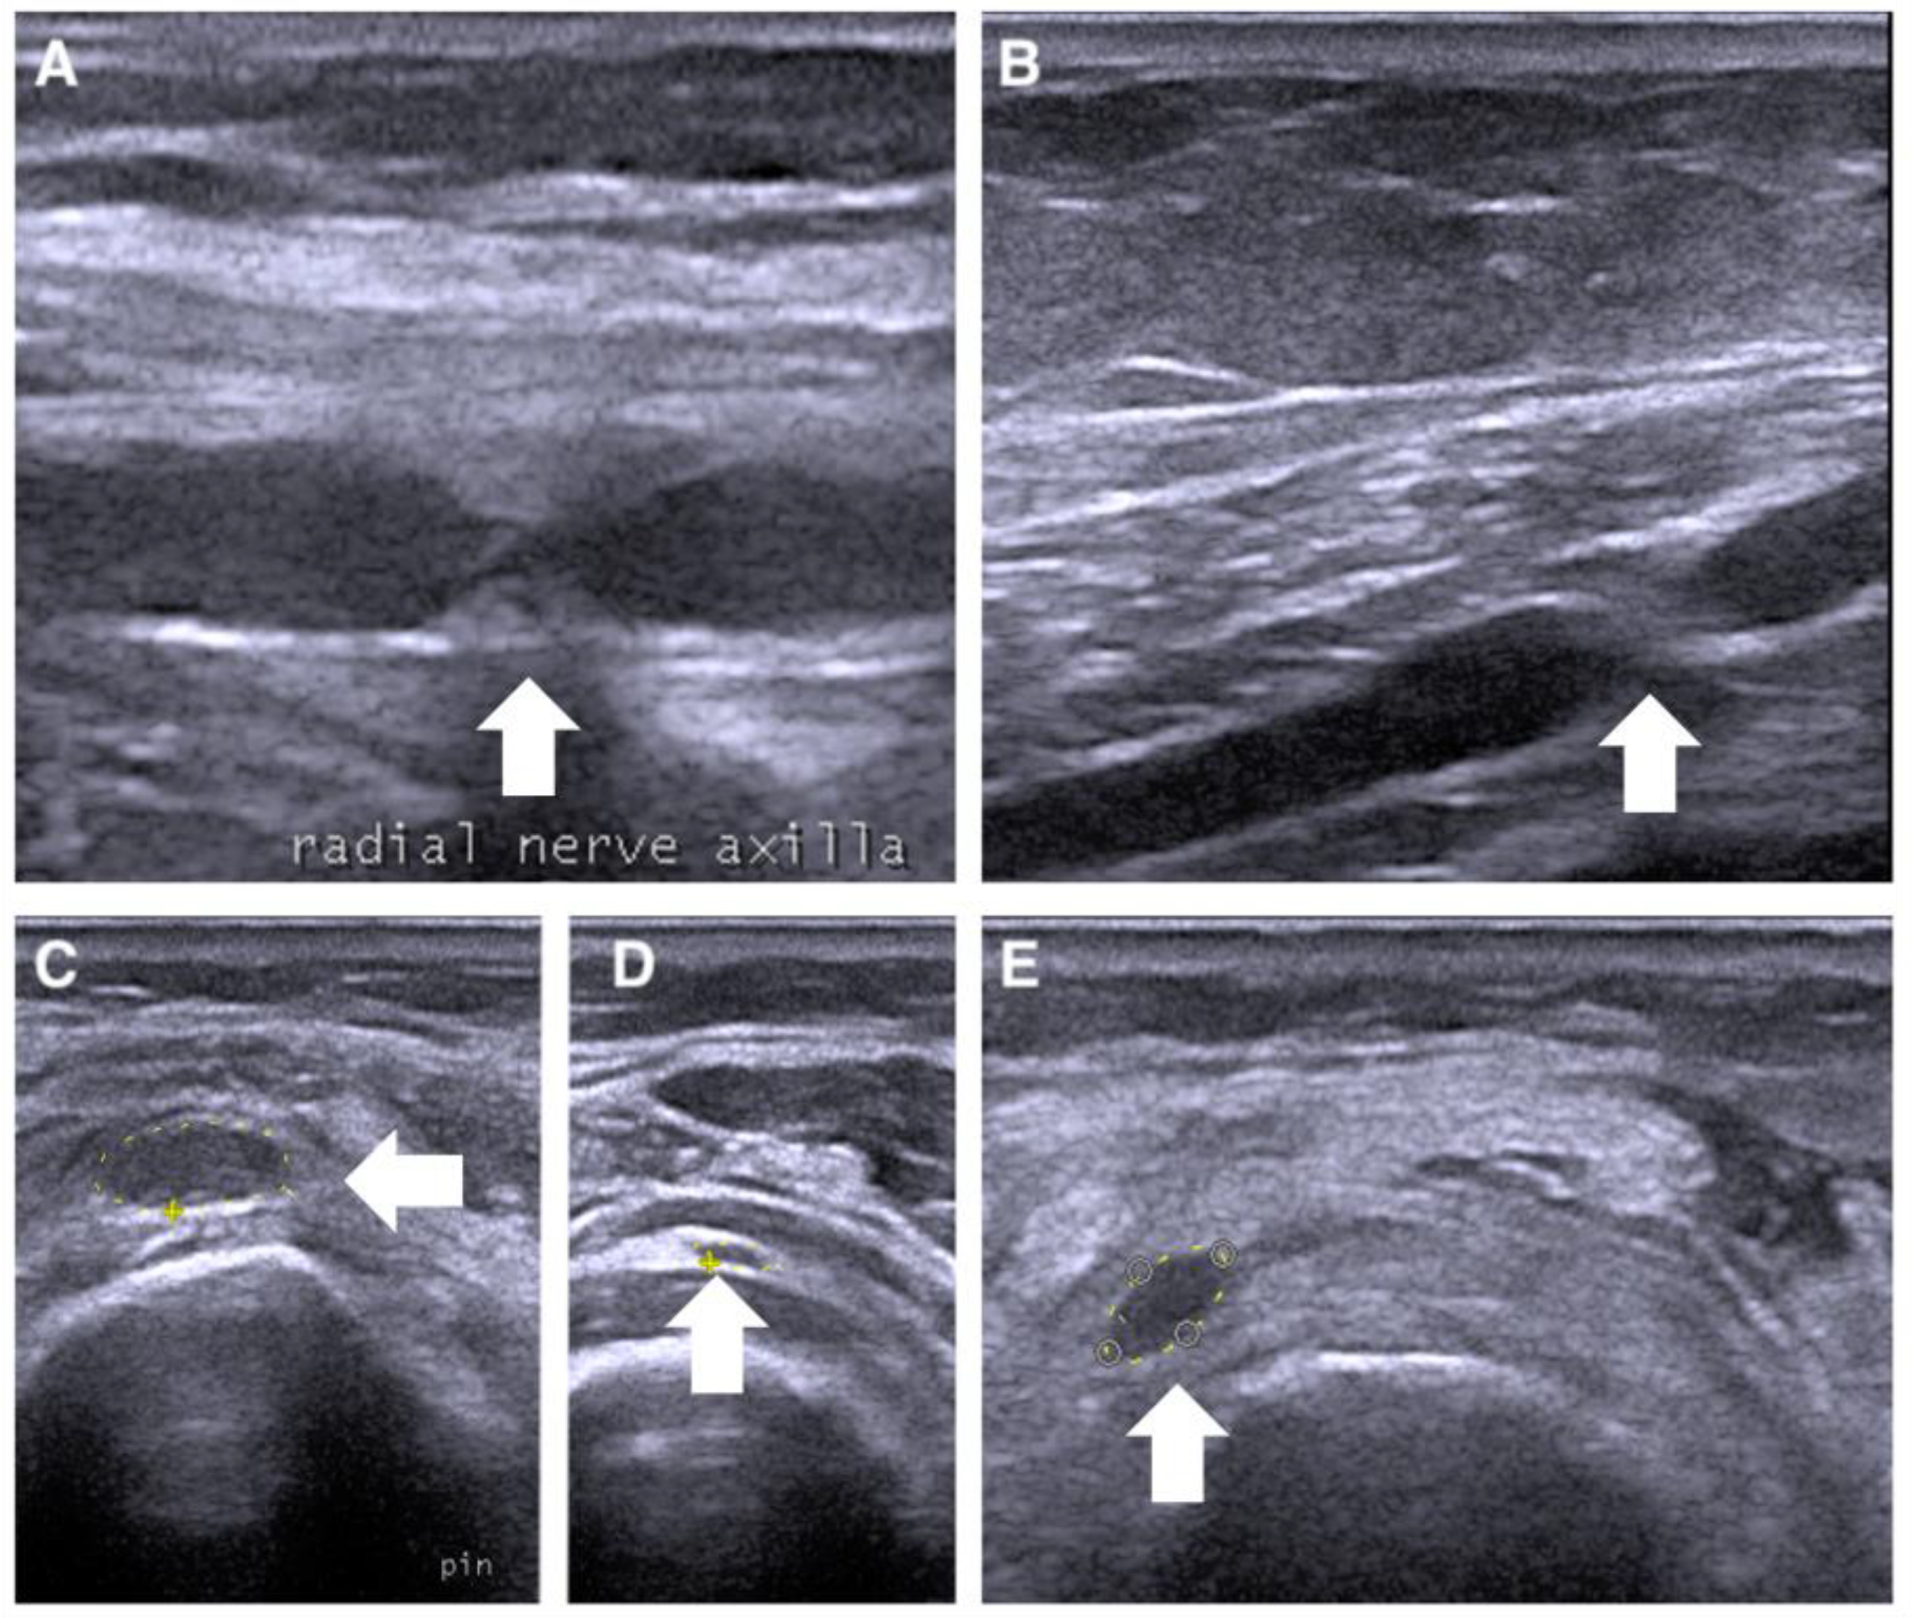

3.1. Case 1

3.2. Case 2